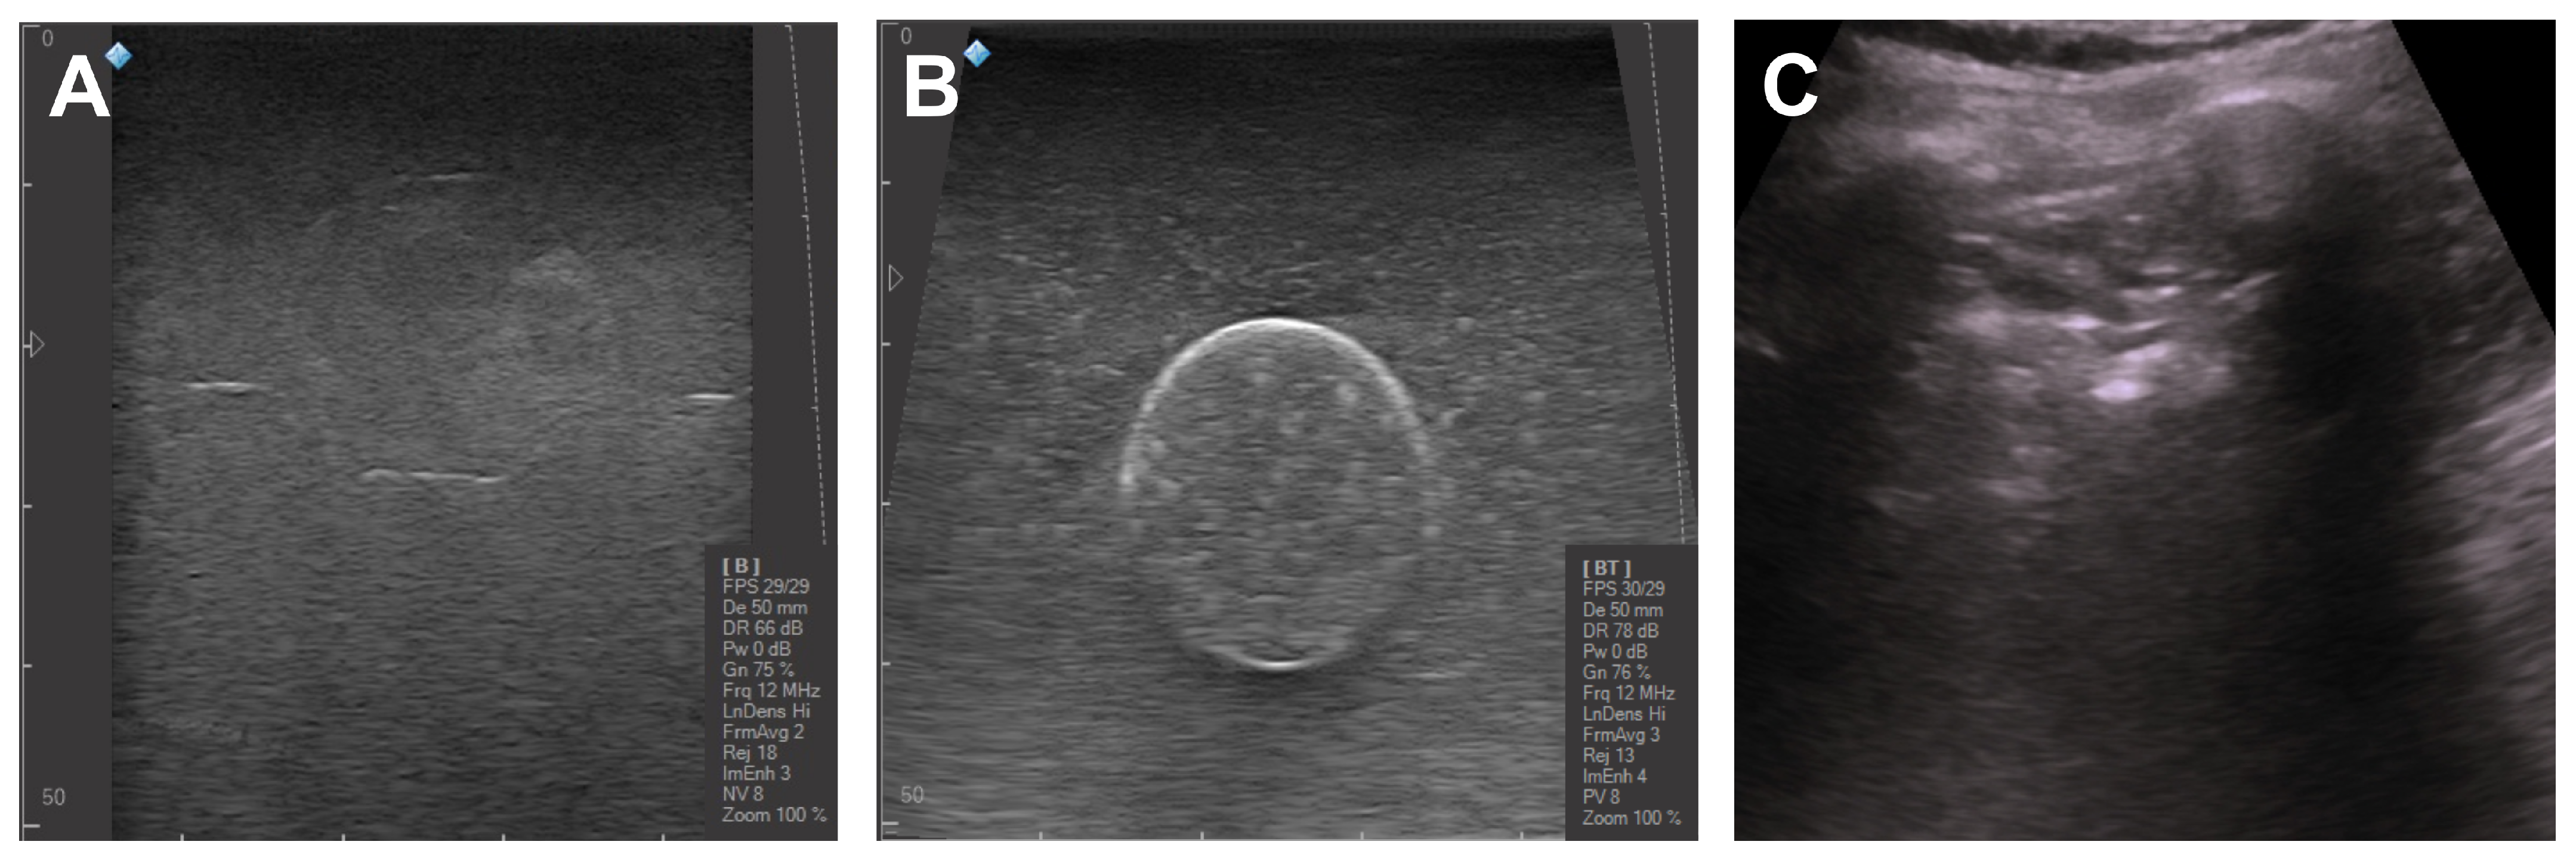

3.2. Ultrasound Imaging